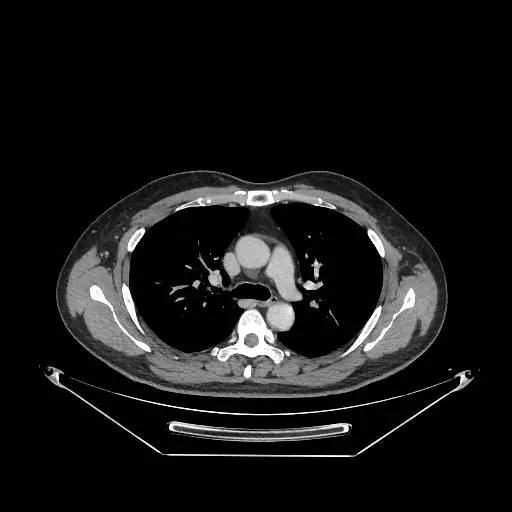

男,47岁,查体发现右肺小结节8月余。

[影像描述]

右肺上叶可见直径约7mm磨玻璃样结节,其内见空泡影,有浅分叶及血管集束征象,增强扫描无强化,余肺、纵隔未见明显异常。

右肺上叶不典型腺瘤样增生(AAH)

AAH的影像学特点为呈类圆形小病灶,边界清楚,淡至中等密度均匀的毛玻璃或磨砂玻璃阴影,不遮蔽其下的肺实质,多数在5 mm以下。